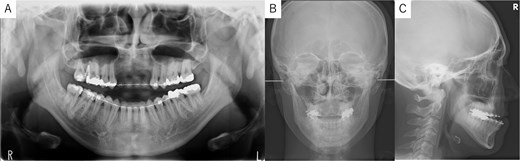

A 26-year-old man was referred to our department in February 2023 for surgical orthodontic treatment and bone grafting. He had experienced tooth loss and an alveolar bone defect due to trauma at the age of 2 years. The patient was 174.5 cm tall, weighed 69.7 kg, and showed normal nutritional and blood test results. His facial features were symmetrical, with a straight lateral profile and mandibular protrusion (Fig. 1A). Intraoral examination revealed missing bilateral maxillary central incisors, lateral incisors, and canines, along with an anterior maxillary alveolar bone defect. Temporary anterior teeth were present, with an overbite of +1 mm and an overjet of −7.3 mm. The maxillary and mandibular midlines aligned with the facial midline (Fig. 1B). A panoramic radiograph confirmed the tooth loss and alveolar defect (Fig. 2A), while cephalometric radiographs showed no chin deviation (Fig. 2B and C). Lateral cephalometric analysis (Table 1) revealed that the maxilla aligned with the anterior cranial floor and that the mandible had a high angle, consistent with skeletal mandibular protrusion. The clinical diagnosis was an alveolar bone defect in the maxillary anterior region and skeletal mandibular protrusion with a dolichofacial pattern.

Panoramic radiograph and cephalogram. (A) Panoramic radiograph showing bone loss in the maxillary anterior region from the right to left canine. (B) Frontal cephalogram showing no chin deviation. (C) Lateral cephalogram indicating skeletal mandibular protrusion.